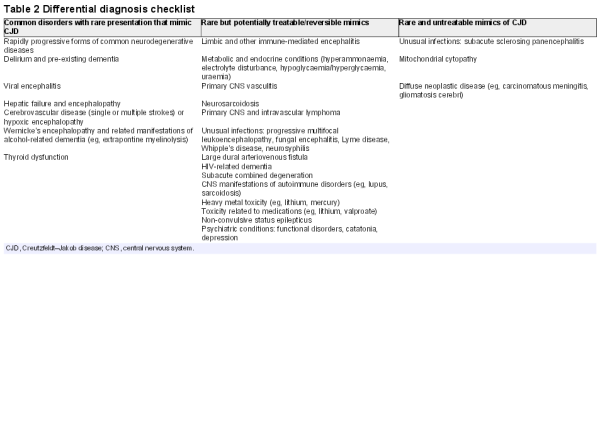

While we list the obvious conditions that a neurologist would consider after an initial assessment, it is usually clear that the patient warrants urgent and comprehensive investigation. At an initial assessment, the rapidity of progression may not be evident, either because there is no witness account available or because comorbidities or prodromal symptoms obscure the underlying disease. Some interventions are therefore indicated immediately while waiting for initial test results. Suspect cases of viral encephalitis should be treated with intravenous acyclovir. Cases associated with weight loss, alcohol excess or other evidence of malnutrition should be treated with intravenous vitamins. In all patients, we recommend a blood screen, including routine haematology, biochemistry, thyroid function, vitamin B12, serology for neurosyphilis, paraneoplastic antibodies and serology for limbic encephalitis; MR scan of brain (dementia protocol), including axial diffusion-weighted imaging and fluid-attenuated inversion recovery (FLAIR); electroencephalograph (EEG) and cerebrospinal fluid (CSF) examination for basic constituents, 14-3-3 protein, S100b, abeta and tau proteins, and the real-time quaking-induced conversion assay (RT-QUIC) (table 1).

Imaging

MR imaging of brain is an extremely useful investigation in CJD, because it is readily available at short notice and non-invasive. Classical abnormalities are high signal on diffusion-weighted imaging or FLAIR in the striatum, cerebral cortex and/or thalamus (figure 2). Changes at these three sites may occur in isolation or combination. Cortical signal change is often patchy and extensive but should involve more than one cortical region and areas that are not vulnerable to artefactual signal change (eg, the frontal pole) and should not enhance or show mass effect. Thalamic signal change may be diffuse or have emphasis in dorsal and medial aspects but should not be of greater signal intensity than in the striatum in sporadic CJD. Most units report a sensitivity of MRI>90% in the diagnosis of sporadic CJD. In grey matter, CJD is associated with small vacuoles in neuronal cell bodies, axons or dendrites, which are most probably the pathological substrate for imaging abnormalities. Often, cortical signal change correlates with clinical features, for example, contralateral in the frontal lobe in patients with hemiparesis or occipital cortex signal change in the visual variant of CJD. Post-gadolinium imaging can help identify blood–brain barrier breakdown in lymphoma and neuroinflammatory conditions, which is not seen in CJD.

Figure 2

Typical MRI features of Creutzfeldt-Jakob disease (CJD). (A and B) Sporadic CJD showing typical basal ganglia signal return on fluid-attenuated inversion recovery (FLAIR) (A), which is more obvious on diffusion-weighted sequences (B). (C) Diffusion-weighted imaging sequence showing striking cortical ribboning with normal basal ganglia in sporadic CJD. (D) Variant CJD showing pulvinar sign on the FLAIR sequence.